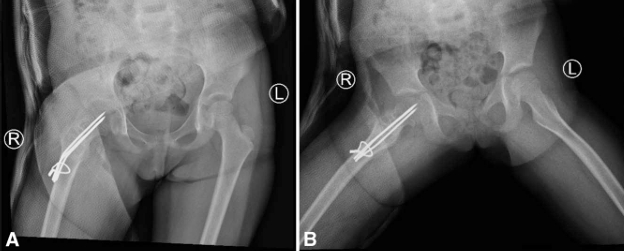

A. Anteroposterior pelvic radiograph showing a multiloculated osteolytic lesion in the right femoral neck extending from the growth plate to the intertrochanteric line, associated with cortical disruption (stress fracture) and varus displacement.

B. Frog-leg lateral radiograph confirming the same findings.

Imaging showed:

• A large osteolytic lesion in the right femoral neck extending into the trochanteric region

• Stress fracture of the femoral neck

• Varus displacement

(See Figures 1 and 2)